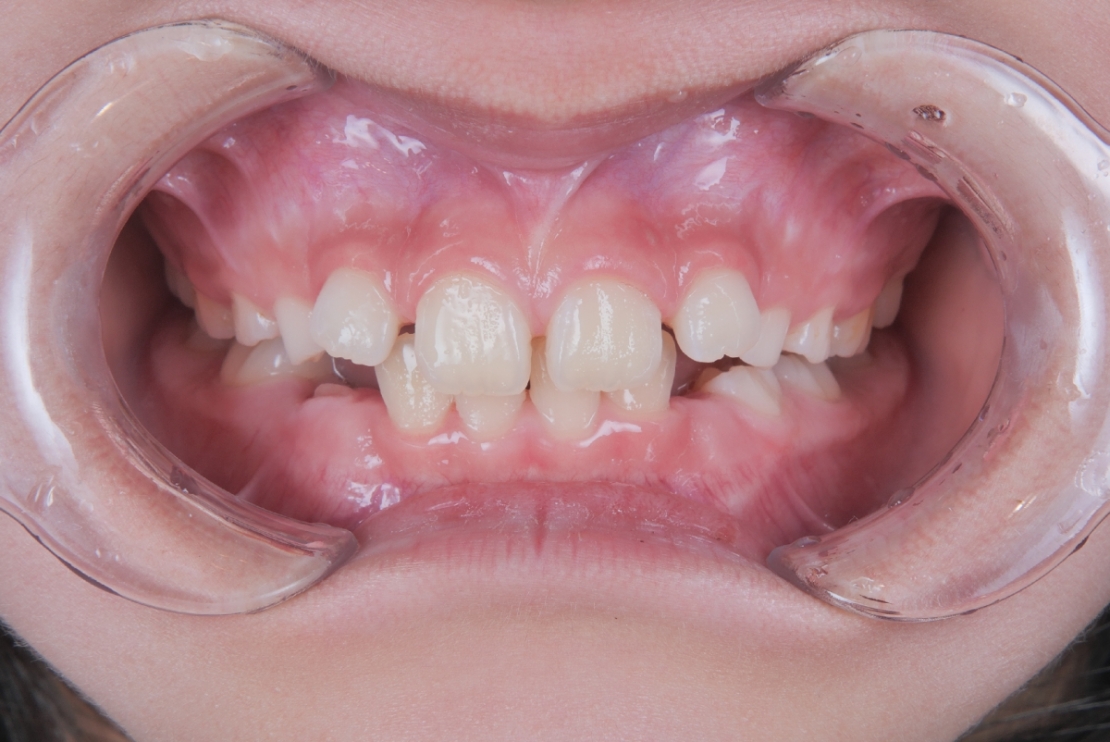

BEFORE

スタート時8歳の女の子の症例です。主訴は歯並びのガタつきと、上の2番目の歯が八重歯のようにハの字に傾いていることでした。

治療は、マウスピース矯正インビザライン・ファーストにて矯正治療を行い、成長を活かしながら歯列を整えていきました。治療期間はわずか11ヶ月で完了し、ガタつきと歯の傾きは改善しています。

| 施術内容 | プレオルソ+歯全体のマウスピース矯正システム「インビザラインファースト」を用いた治療 |